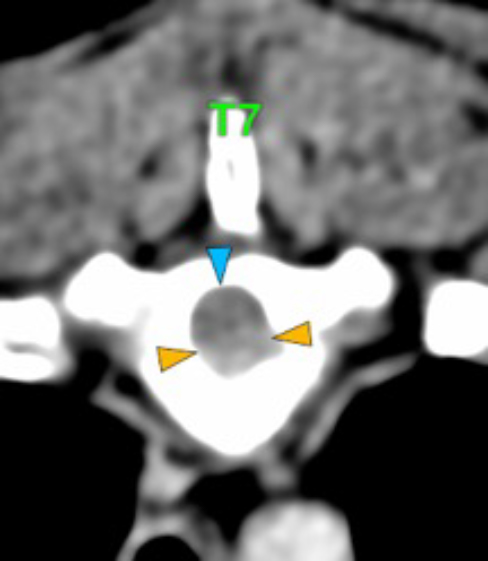

The osteolytic lesions have soft tissue attenuation that shows moderate and slightly heterogeneous post-contrast enhancement. In some of the vertebrae, the lesions cause lysis of the cortex and extend into the vertebral canal (orange arrows) causing variable degree of compression of the spinal cord and cauda equina (blue arrows). At the level of the vertebral bodies of T7, T8, T9 and T12 the lesions extend into the ventral and central aspect of the vertebral canal causing a mild compression of the spinal cord. At the level of T13, L1, L4 and L5 the lesions extend into the ventral and central aspect of the vertebral canal, causing moderate compression of the spinal cord. At the vertebral body of L6 the lesion extends into the ventral and central aspect of the vertebral canal, at the mid-aspect of L6, occupying approx. 90% of the diameter of the vertebral canal causing a severe compression of the cauda equina. At the level of L7, the lesion extends into the ventral and both lateral aspects of the vertebral canal, causing severe compression of the cauda equina.